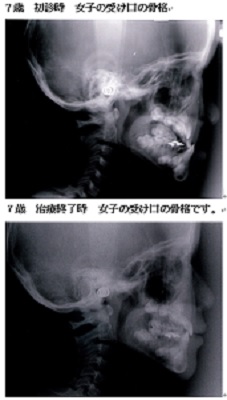

本日ご紹介する症例は7歳の女の子です。典型的な受け口(下顎前突)です。

受け口(下顎前突)だったので上顎骨の成長が抑制されていたために治療後に上顎骨はかなり大きくなっています。

治療前の状態にしておくと将来、顔貌や呼吸機能、顎関節などに異常をきたす可能性がある為早期の治療が望まれます。 -

また、特に受け口(下顎前突)は上下の咬み合わせが通常と逆になるため筋肉や骨の形が通常と変わってきます。そのため受け口は将来の顔貌にも影響を与える為に特に早期の治療

が治療効果を発揮する症例と言えます。いずれも、顎のラインがスッキリしています。

これは、受け口が改善して筋肉の使い方が通常に戻ったために起こった変化です。

大人ではこの変化は起こりません。次に骨格で比べて診ましょう。

同じ人の1年後の骨格です。

小学校低学年の治療であれば、この変化は普通に起こる変化です。

骨格のことからも受け口は早期治療の効果が得られやすい症例です。